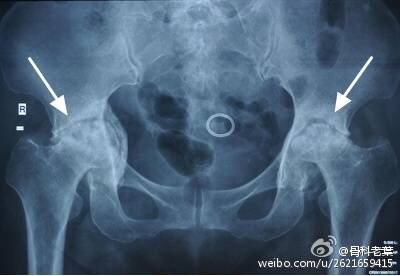

II期 病人有髋部症状,磁共振出现异常,X线片显示股骨头出现透光和硬化改变

III期 磁共振出现异常,X线片显示软骨下塌陷(新月征),股骨头内出现空洞,股骨头没有变扁

II期和III期的患者治疗方法相同,因为此时股骨头虽然还没有变形,暂时还不需要行人工关节置换术,但是股骨头已经出现空洞,随时股骨头就会塌陷变形,所以单纯的股骨头减压术是不能达到治疗效果的。这时就需要在股骨头减压的同时,植入一根支撑棒,顶住股骨头空洞区,防止股骨头在负重的情况下过早塌陷。其他治疗同之前相同,口服以上药物,定期复查,密切观察病情发展,尽量避免重体力劳动和爬山爬楼。